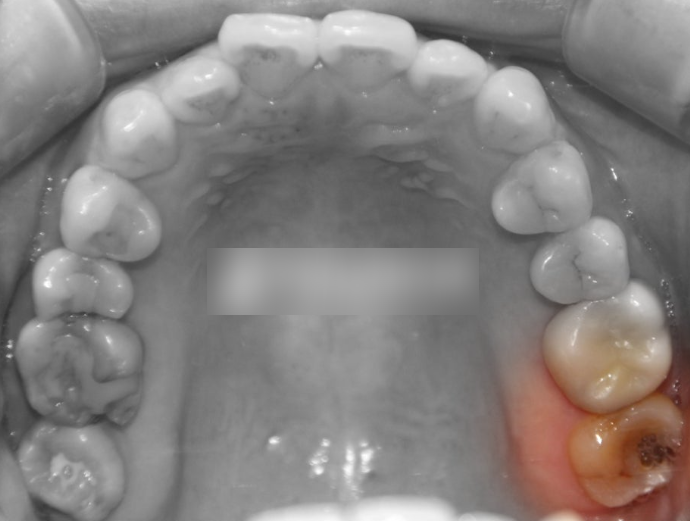

문제점 파악

하단 예시 사진을 관찰해보면

심하게 썩어 있는 최후방구치(# 27)을

확인할 수 있습니다.

이미 치관 부위 부식이 일어나

깨져 있는 것을 볼 수 있습니다.

위쪽 맨 뒤에 있는 어금니에 위치해 있기에

문제가 생기면 쉽게 알아차리기

어려운 편에 속합니다.

하악의 경우는 입을 벌리면 볼 수 있지만,

상악은 육안으로 발견하기가 쉽지 않습니다.